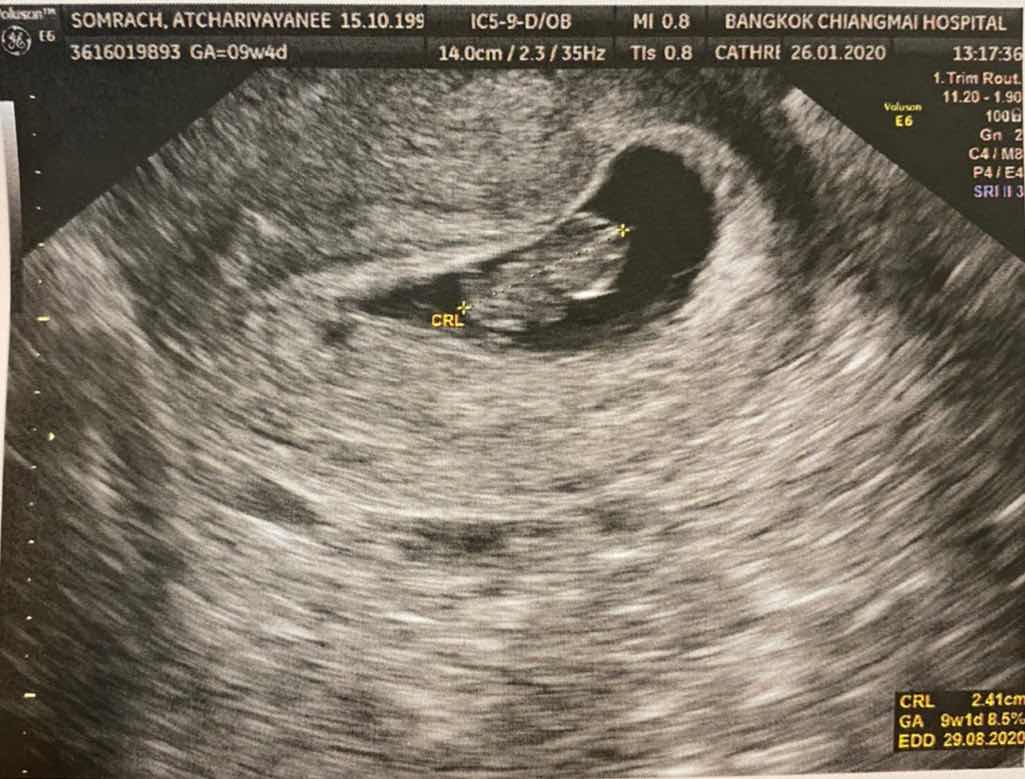

9 week 4day ค่ะ